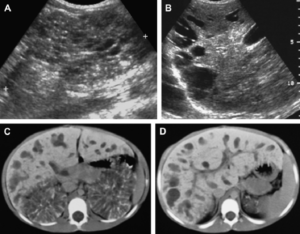

Существует несколько типов эхогенных включений, по которым определяется патологическое состояние почек. Гиперэхогенные включения и разделяются на две большие группы: камни (песок) и новообразования. Чаще всего гиперэхогенные образования располагаются в толще почечных пирамид и паренхиме. На ультразвуковом обследовании выявляются следующие виды образований в почках:

Мелкие включения, не имеющие акустической тени, на экране высвечиваются в виде ярких точек;Образования большого размера, встречающиеся достаточно редко и являющиеся доброкачественными или злокачественными образованиями;Крупные включения в почках. Имеют акустическую тень, и являются злокачественными новообразованиями. Это может подтвердиться также наличием кальцификатов и псаммомных телец в опухоли, а также склерозированными участками.

Кистозное образование;Склерозирование почечных сосудов;Жировые образования пирамидок почек;Абсцесс, карбункул;Гематома (кровоизлияние).

Затем рассматривается структура и строение паренхимы. Появление крупных образований высокой плотности вызвано образованием камней при мочекаменной болезни или развитием очагового воспалительного процесса.

Участки низкой плотности могут возникнуть при кисте почки, гематоме.

Особое внимание надо обратить на яркие, белые включения, которые указывают на наличие в почках склеротической ткани, кальцификатов и псаммомных телец (белково-жировые комплексы), присущих злокачественным новообразованиям.

- Мелкие включения, не имеющие акустической тени, на экране высвечиваются в виде ярких точек;

- Образования большого размера, встречающиеся достаточно редко и являющиеся доброкачественными или злокачественными образованиями;

- Крупные включения в почках. Имеют акустическую тень, и являются злокачественными новообразованиями. Это может подтвердиться также наличием кальцификатов и псаммомных телец в опухоли, а также склерозированными участками.

- Кистозное образование;

- Склерозирование почечных сосудов;

- Жировые образования пирамидок почек;

- Абсцесс, карбункул;

- Гематома (кровоизлияние).